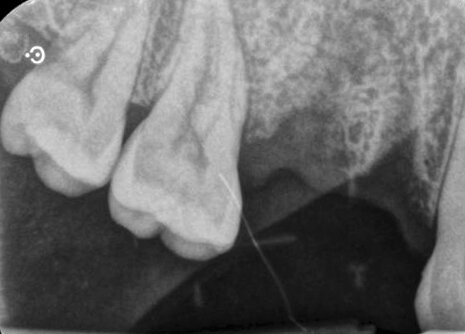

Fig. 1_Radiografia periapicale a 8 settimane dall’estrazione di 14 e 15.